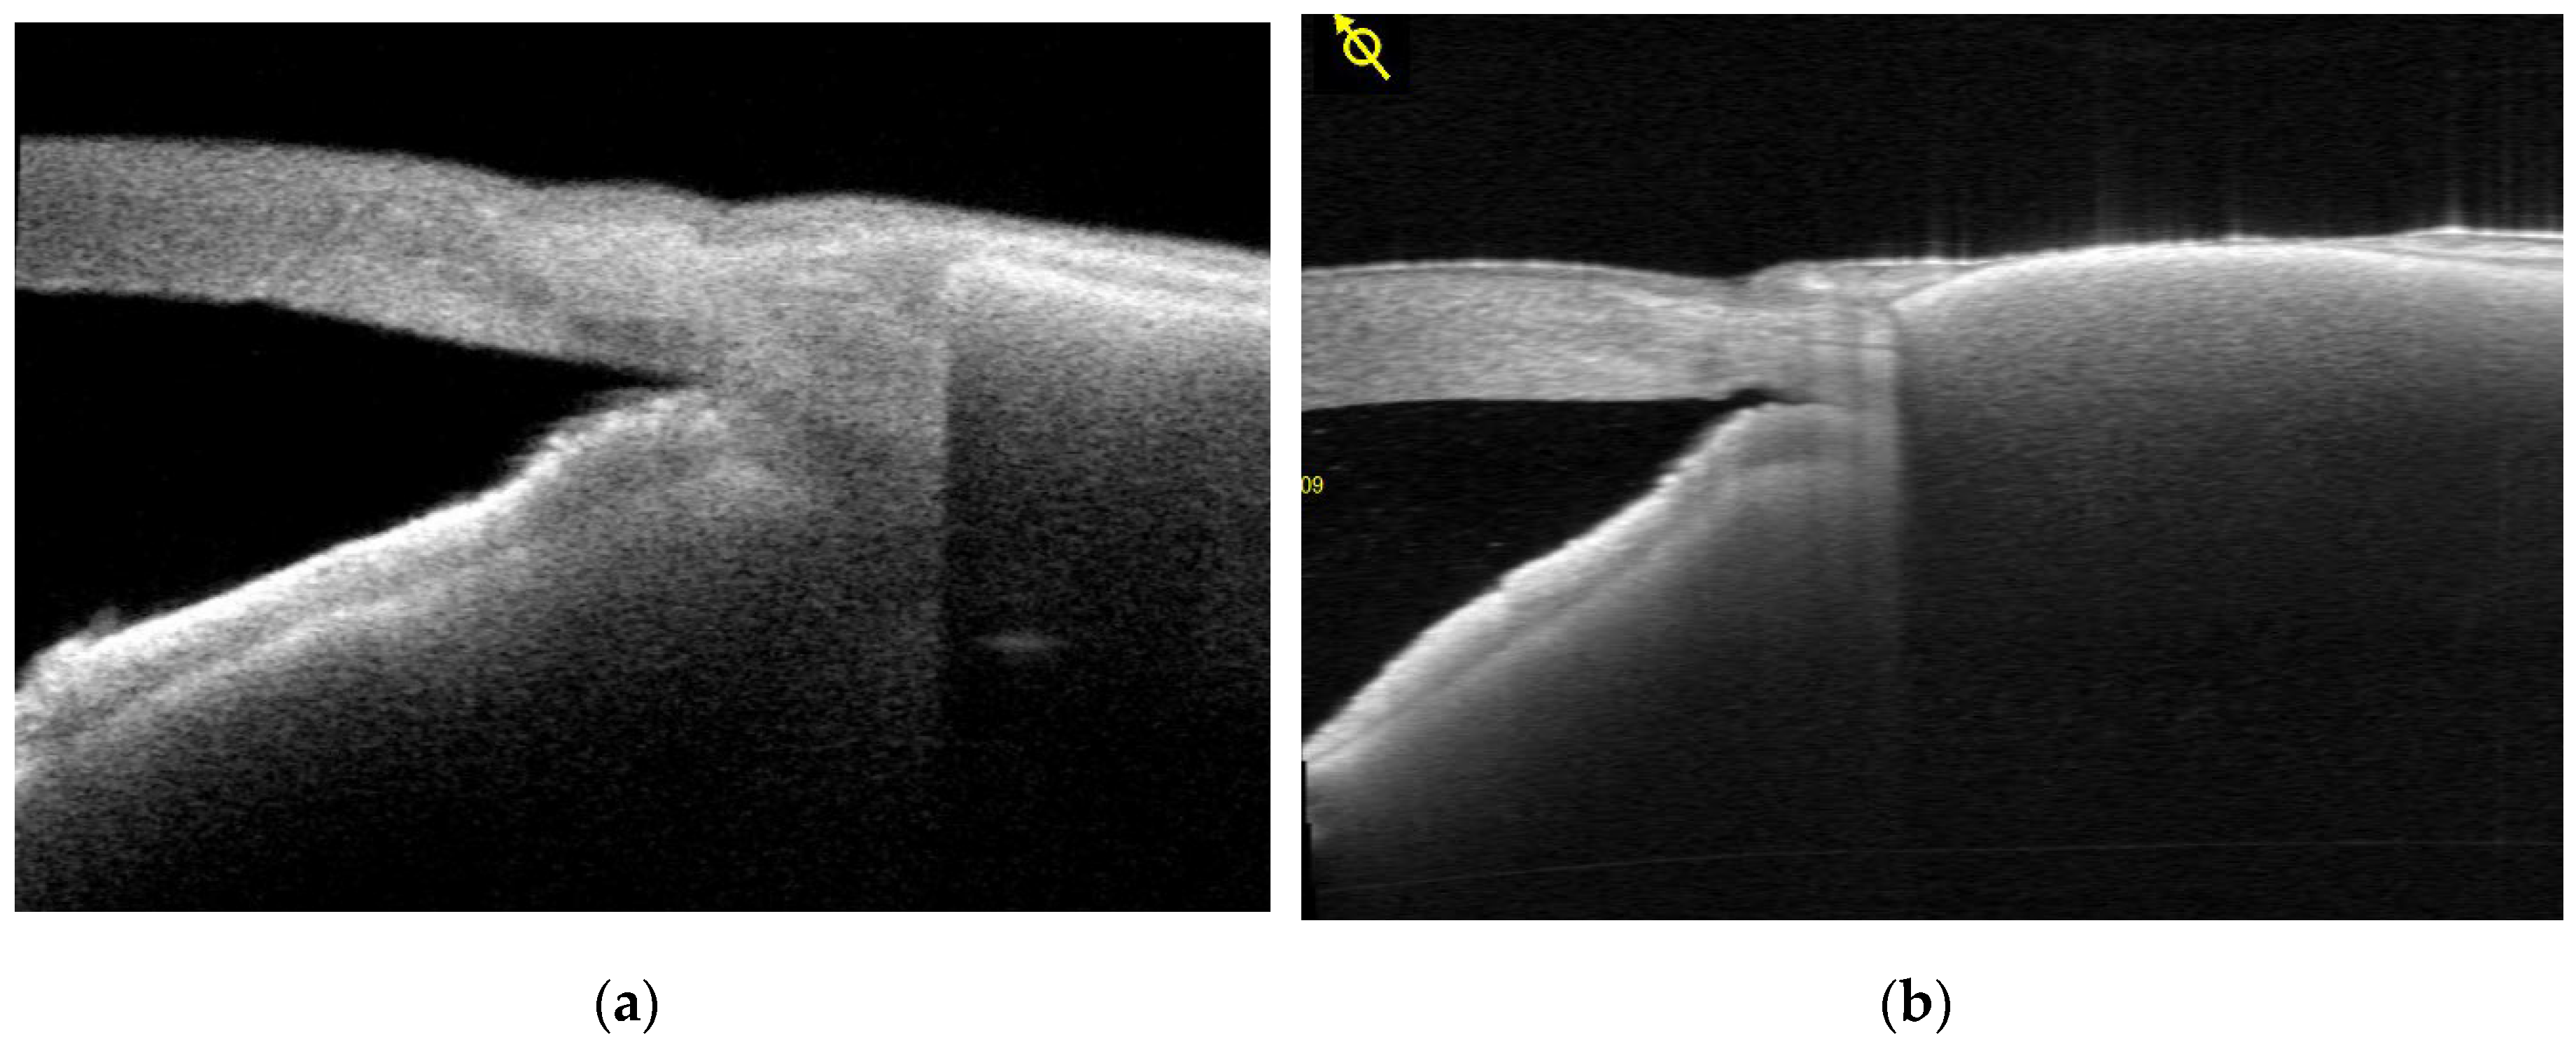

Two distinct patterns of EverPatch extrusion were identified. In one of the three extruded cases, the edge of the EPP mechanically disrupted the overlying conjunctiva leading to exposure of the EPP (Figure 6 a,b). The clinical course in this case was comparable to that observed in conventional scleral patch graft-related extrusion.

A different pattern of extrusion was observed in 2 of 19 eyes treated with EPP, characterized by conjunctival bleaching followed by progressive melting of the overlying conjunctiva. The initial ischemic change developed in the anterior central portion of the EPP. (Figure 7 a, b). This pattern of extrusion was not observed in any of the 12 scleral patch graft cases with extrusion, representing a statistically significant difference between groups (P=0.024 Fischer exact test).

Figure 6. a, b. Destruction of the conjunctiva at the margin of EPP. Vertical misalignment or edge lifting of the EPP resulted in disruption of the overlying conjunctiva.

Figure 7. a, b. Slit-lamp findings in a case of central-type extrusion. Representative slit-lamp photographs illustrating the clinical course of an EPP extrusion case. (7a) Appearance at 6.7 months postoperatively. Prior to extrusion, demonstrating decreased vascularity over the anterior central portion of the patch. (7b) Appearance at 8.9 months postoperatively, showing progression to conjunctival melting and subsequent patch exposure. This type of extrusion began as a small dimple in the central area of EPP and progressed rapidly, leading to conjunctival melting and subsequent exposure of the patch.